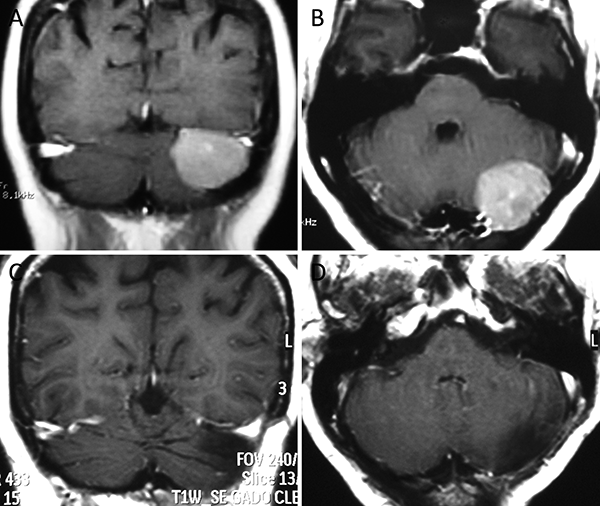

Figura 3. Meningioma clival. A-B: RM preoperatoria; C-D: RM postoperatoria.